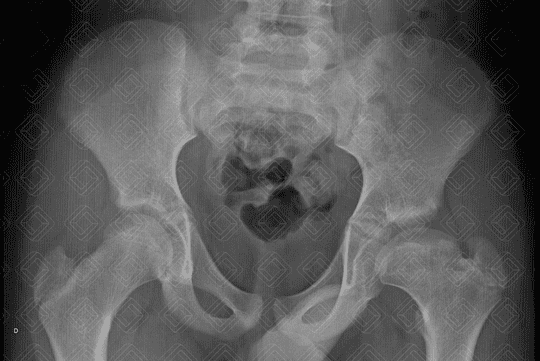

Texto alternativo para a imagem Figura 1. Créditos: Dra. Elazir Mota - Rio de Janeiro/RJ

Descrição da lesão: Legg-Calvé-Perthes (necrose avascular idiopática).

Descrição das imagens: Radiografia de bacia em AP (figura 1) e Lowenstein ou posição de rã (figura 2): redução da altura e osteopenia da epífise femoral esquerda associada a colo femoral alargado e encurtado a este lado. Quadril direito sem alterações.

Doença de Legg-Calvé-Perthes: Necrose avascular (osteonecrose) idiopática da cabeça femoral. Seu pico de incidência é entre 2-14 anos de vida, mais comumente ao redor dos 6 anos. Os meninos são mais acometidos (5:1). A etiologia da doença permanece incerta.

• Radiografia do quadril: S empre realizar estudo em AP e Lowenstein (posição da rã). Numa fase muita aguda, os achados da osteonecrose na radiografia são sutis. Com o passar das semanas e meses, observamos redução da altura das imagens e lesões líticas e, mais tardiamente, fragmentação e destruição óssea;